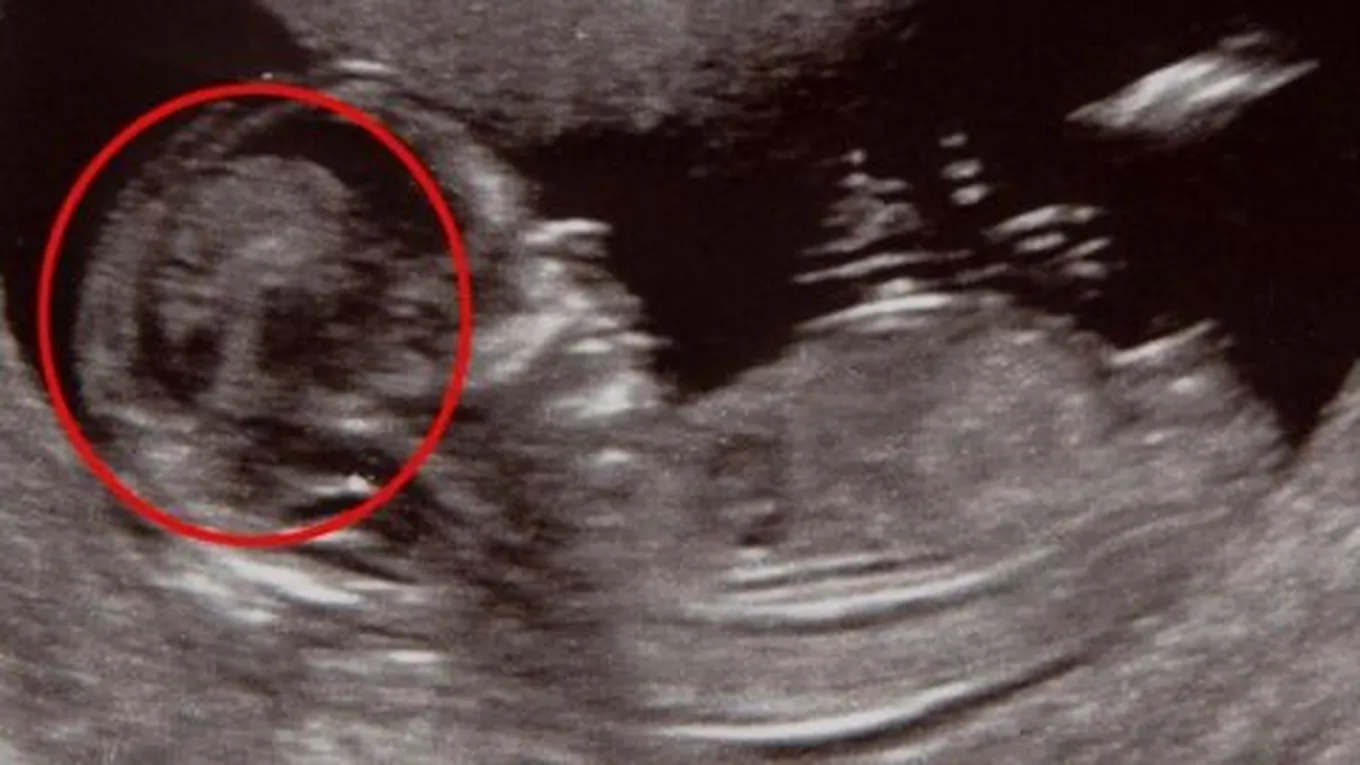

إنَّ جهاز السونار أو Ultrasound من الأجهزة الَّتي أثبتت جدارتها عن حق، فقد ساعدت الإنسان على معرفة بعض التفاصيل الهامّة والتشخيصيّة على مستوى عميق من جسم الإنسان، الَّتي قد يكون لها تأثير كبير في تلقّيه للعلاج المُناسب، وواحدة من أهم استخدامات السونار هي: رؤية الجنين، ومعرفة جنسه، والتأكّد من صحّته وسلامته، ويعدّ توفر هذا الجهاز نعمة من الله تعالى، فقد ساعد الكثير من الأمهات والآباء على رؤية طفلهم قبل ولادته، والتأكّد من سلامته وصحّته، ويُمكن رؤية الجنين على السونار بدءاً من الأشهر الثلاث أو الأربع الأولى من الحمل، ففي تلك الفترة يمكن للوالدين رؤية طفلهما للمرَّة الأولى، وعادةً ما يُستخدم جهاز Transabdominal Ultrasound خلال فترة الحمل لرؤية الجنين.

يُمكن للعديد من السيدات الحصول على معلوماتٍ وافية عن الجنين من خلال جهاز Transabdominal Ultrasound ، وذلك بعد مرور أول ثمانية أسابيع من الحمل، ولكن خلال فترات الحمل الأولى المُبكّرة يكون حجم الجنين صغيراً، فقد يصل طوله في الأسبوع السادس من الحمل من خمسة إلى تسعة ملليمترات، وعندها قد يستخدم الطَّبيب جهاز سونار آخر وهوTransvaginal Ultrasound، وذلك للحصول على رؤيةٍ أوضح للجنين، ويُعدَّ جهاز Transvaginal Ultrasound آمناً، ويُمكن استخدامه خلال كافَّة مراحل الحمل ومنها الثُلث الأول من الحمل، والَّذي يُعدّ الثُلث الأكثر تأثّراً في الحمل، فهذا الجهاز لن يتسبّب في إيذاء الجنين أو الأم.